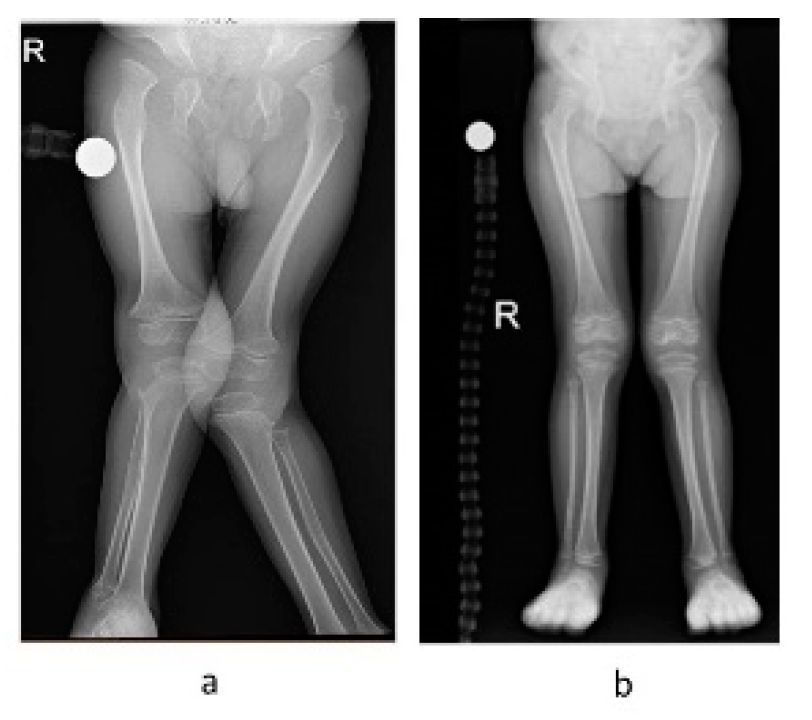

- Orthopedic and radiographic assessments and procedures—orthopedic and radiographic assessments were routinely conducted in order to assess structural changes. As recommended, the radiographic assessments mainly focused on the lower extremities (e.g., presence of progressive hip dysplasia, genu valgus, and ankle valgus), upper extremities, cervical spine, and thoracolumbar spine [31]. All orthopedic procedures were documented.

3.4. Orthopedic and Radiographic Assessments and Procedures

4.3. Clinical Course, and Orthopedic and Radiographic Assessments